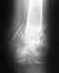

8 месяцев не срастается многооскольчатый перелом в/3 обеих костей правой голени со смещением. Просим Вас помочь. Мужчине 70 лет, ликвидатор Чернобыльской АЭС, резекция 5/6 части желудка. В июне 2019 года получил многооскольчатый перелом обеих костей в/3 правой голени со смещением. В июне поставили аппарат Илизарова. Проходил с ним 4 месяца и безрезультатно. Аппарат сняли и в октябре 2019 года вставили стержень на болтах. К сожалению, в январе 2020 года сделали снимок и срастания нет. стопой шевелит. нога немного сгибается. Просим Вас помочь. Что делать не знаем. Отправляют на инвалидность. Но, хотелось бы поставить папу на ноги. Делать третью операцию? Прилагаю снимок января 2020 года. Есть снимки всех этапов лечения.

Проблема понятна. В принципе, может срастись и в положении как есть. Но лучше бы пересинтезировать хоть тем же стержнем, но с устранением все смещений. Технически это вполне выполнимо, надо только знать и уметь делать все необходимые элементы операции.